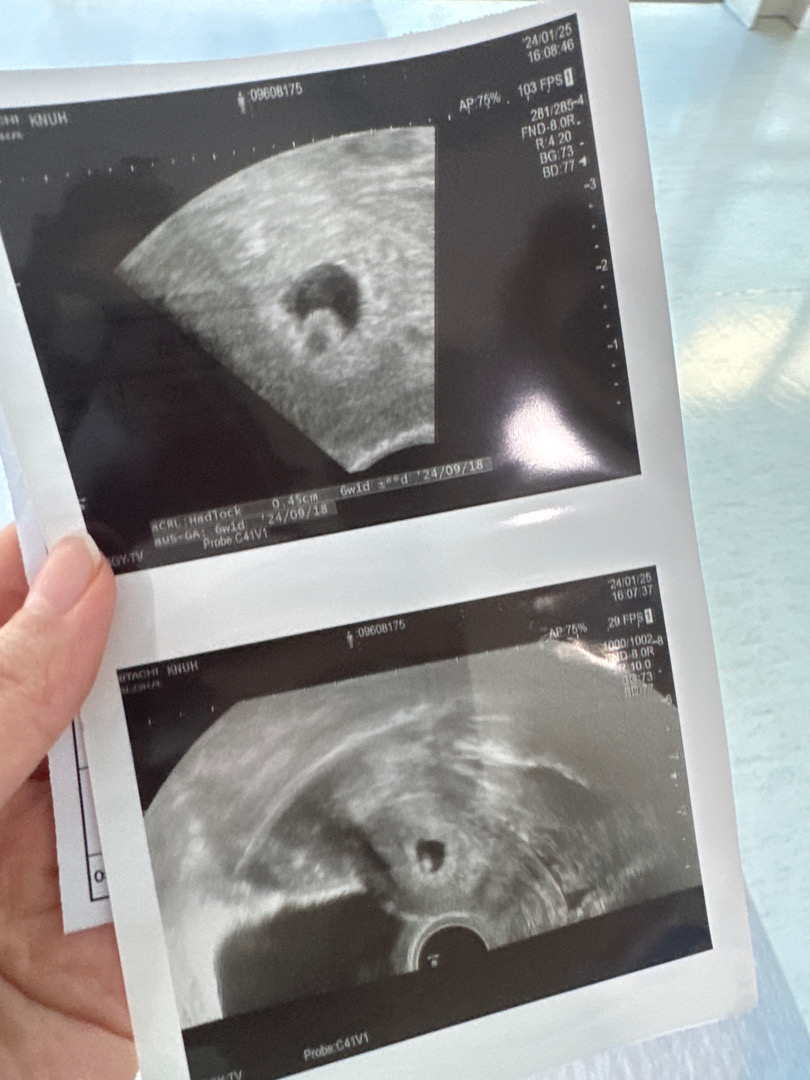

아직은 반지네요~~ 좀더있음 반지는 작아지고 번데기처럼 길쫌하게 보여요~~

저 동글이 뭘로 보여요??

난황인가용 애기인가용 뭔가용?

난황같아요~ 아기는 아직 안보일걸요 ㅎㅎ

난황아닌가요? 아기는 사이즈 재주셨을거에요.

아기가 보이면 난황은 작아져요! 저도 7주차 즈음에 아기보이고 난황이 작아졌어요. 초음파상이라 아기랑 난황이 겹쳐보일 수도 있을 것 같아요.